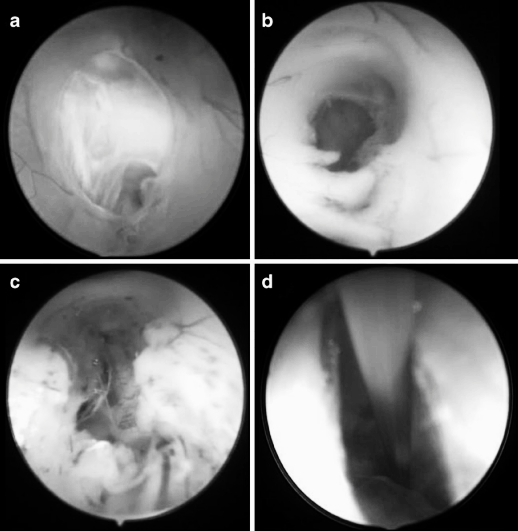

图3 内镜下右侧室间孔的不同形态,提示第三脑室穿刺难度逐渐增大。a 水平型 b 斜向型 c 垂直型 d 垂直且孔径缩小型